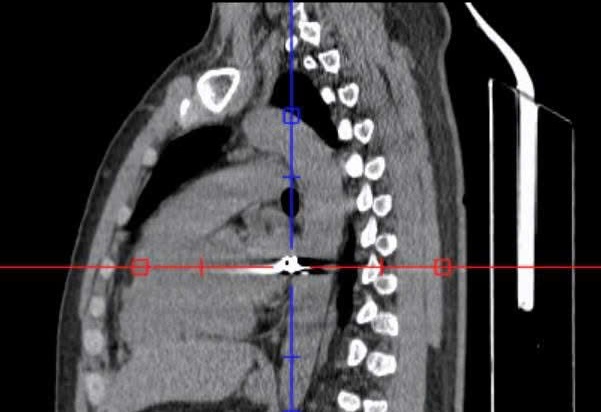

On April 21, Thong Nhat General Hospital in Dong Nai said that it had just successfully saved a male patient named P.V. H (32 years old, residing in Thanh Son commune, Dong Nai province) who was shot in the chest, the bullet path went from the back right to the left.

As a result, after more than 4 hours, the medical team successfully removed a 0.3 x 0.5 cm warhead.